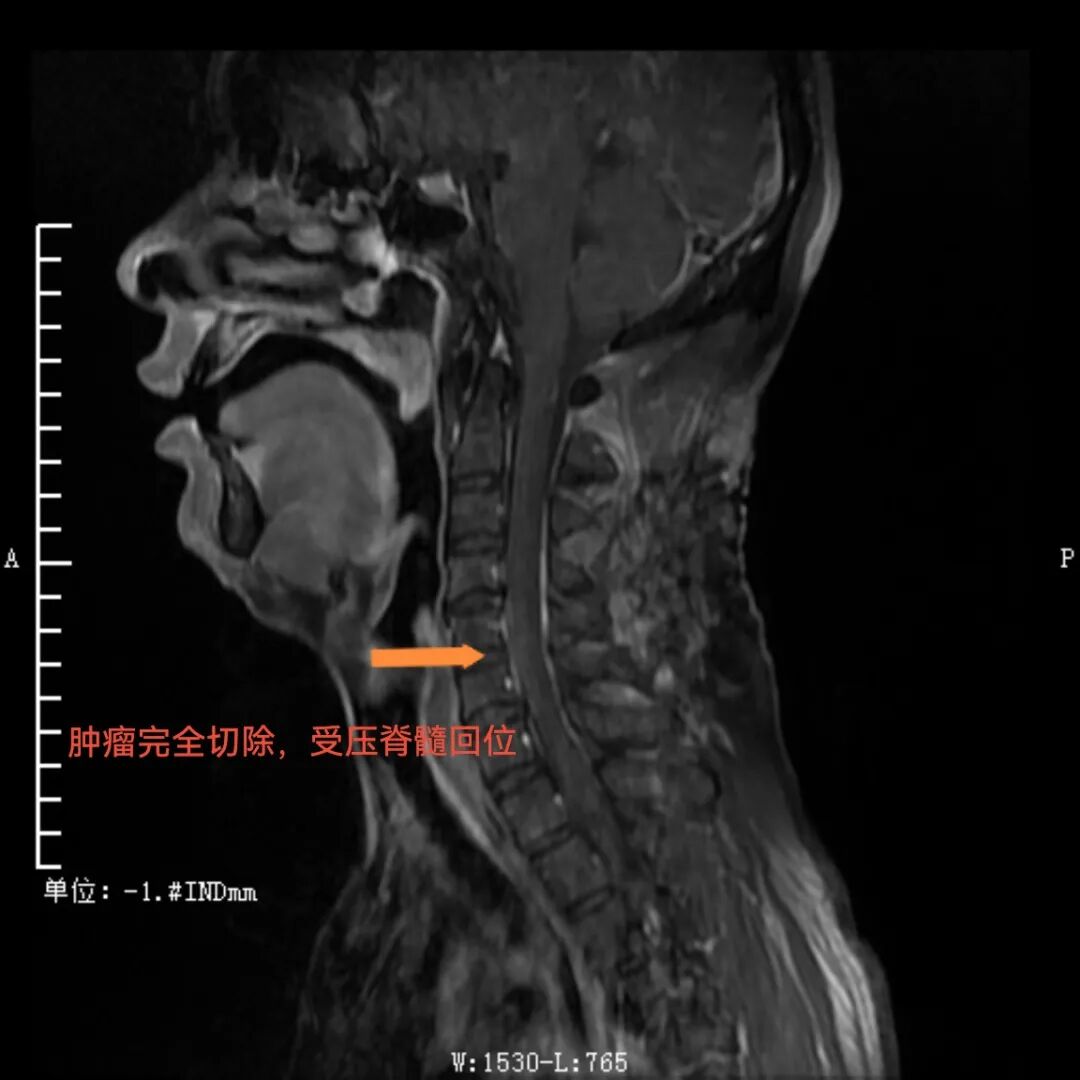

手术过程中,先由脊柱外科团队采取“单开门”的方式打开经4、5节段左侧椎板并向右侧掀起。这种独特的操作方式能够充分暴露肿瘤区域,再由神经外科团队在显微镜下打开硬脊膜并完整切除肿瘤。手术顺利,如今患者已出院,本人及家属对手术效果相当满意,赠送锦旗表示感谢。

术后,肿瘤完全切除,受压脊髓回位